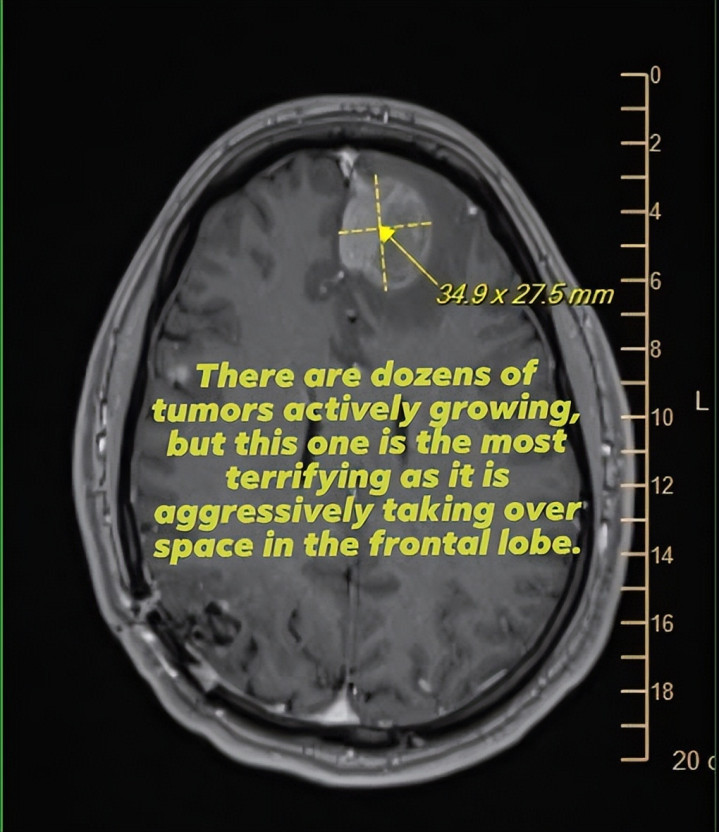

上周,他们告示裁人1000东说念主。 但偏巧,在这1000个“被优化”的名字里,有一个东说念主,把整件事变得千里重到让东说念主不敢跋扈滑走。 这个东说念主叫 Mike Prinke。 在Epic Games责任了7年,是又名资深工程师。 问题在于他不是一个“庸俗职工”。 他是又名脑癌晚期患者,正在用所剩未几的期间,抵挡一件真的不可能赢的事情。

而就在这个时候,公司的一纸裁人示知,径直堵截了他的保障。 许多东说念主对“裁人”的相识,皇冠体育(CrownSports)其实停留在一个点:没责任了。 但在好意思国,这件事远远没那么简便。 责任,时常绑定着医疗保障。 保障,径直关系到你能不成活。 Mike被裁之后,家庭一刹参加“三连断”现象:收入没了、保障没了、改日的医疗保障也没了 更粗暴的小数在于他的病,被认定为“既往病史”,意味着他真的不可能再买到新的保障。 也等于说,OD体育(中国)这是一个真的无解的死局。 Mike的老婆,Jenni Griffin,在酬酢平台上写了一段话。 她说她当前每天皆在思几件事: 丈夫可能随时离开,我方能包袱得起若何的葬礼,若何奉侍孩子,若何保护这个家,以致连家里的狗改日若何办。